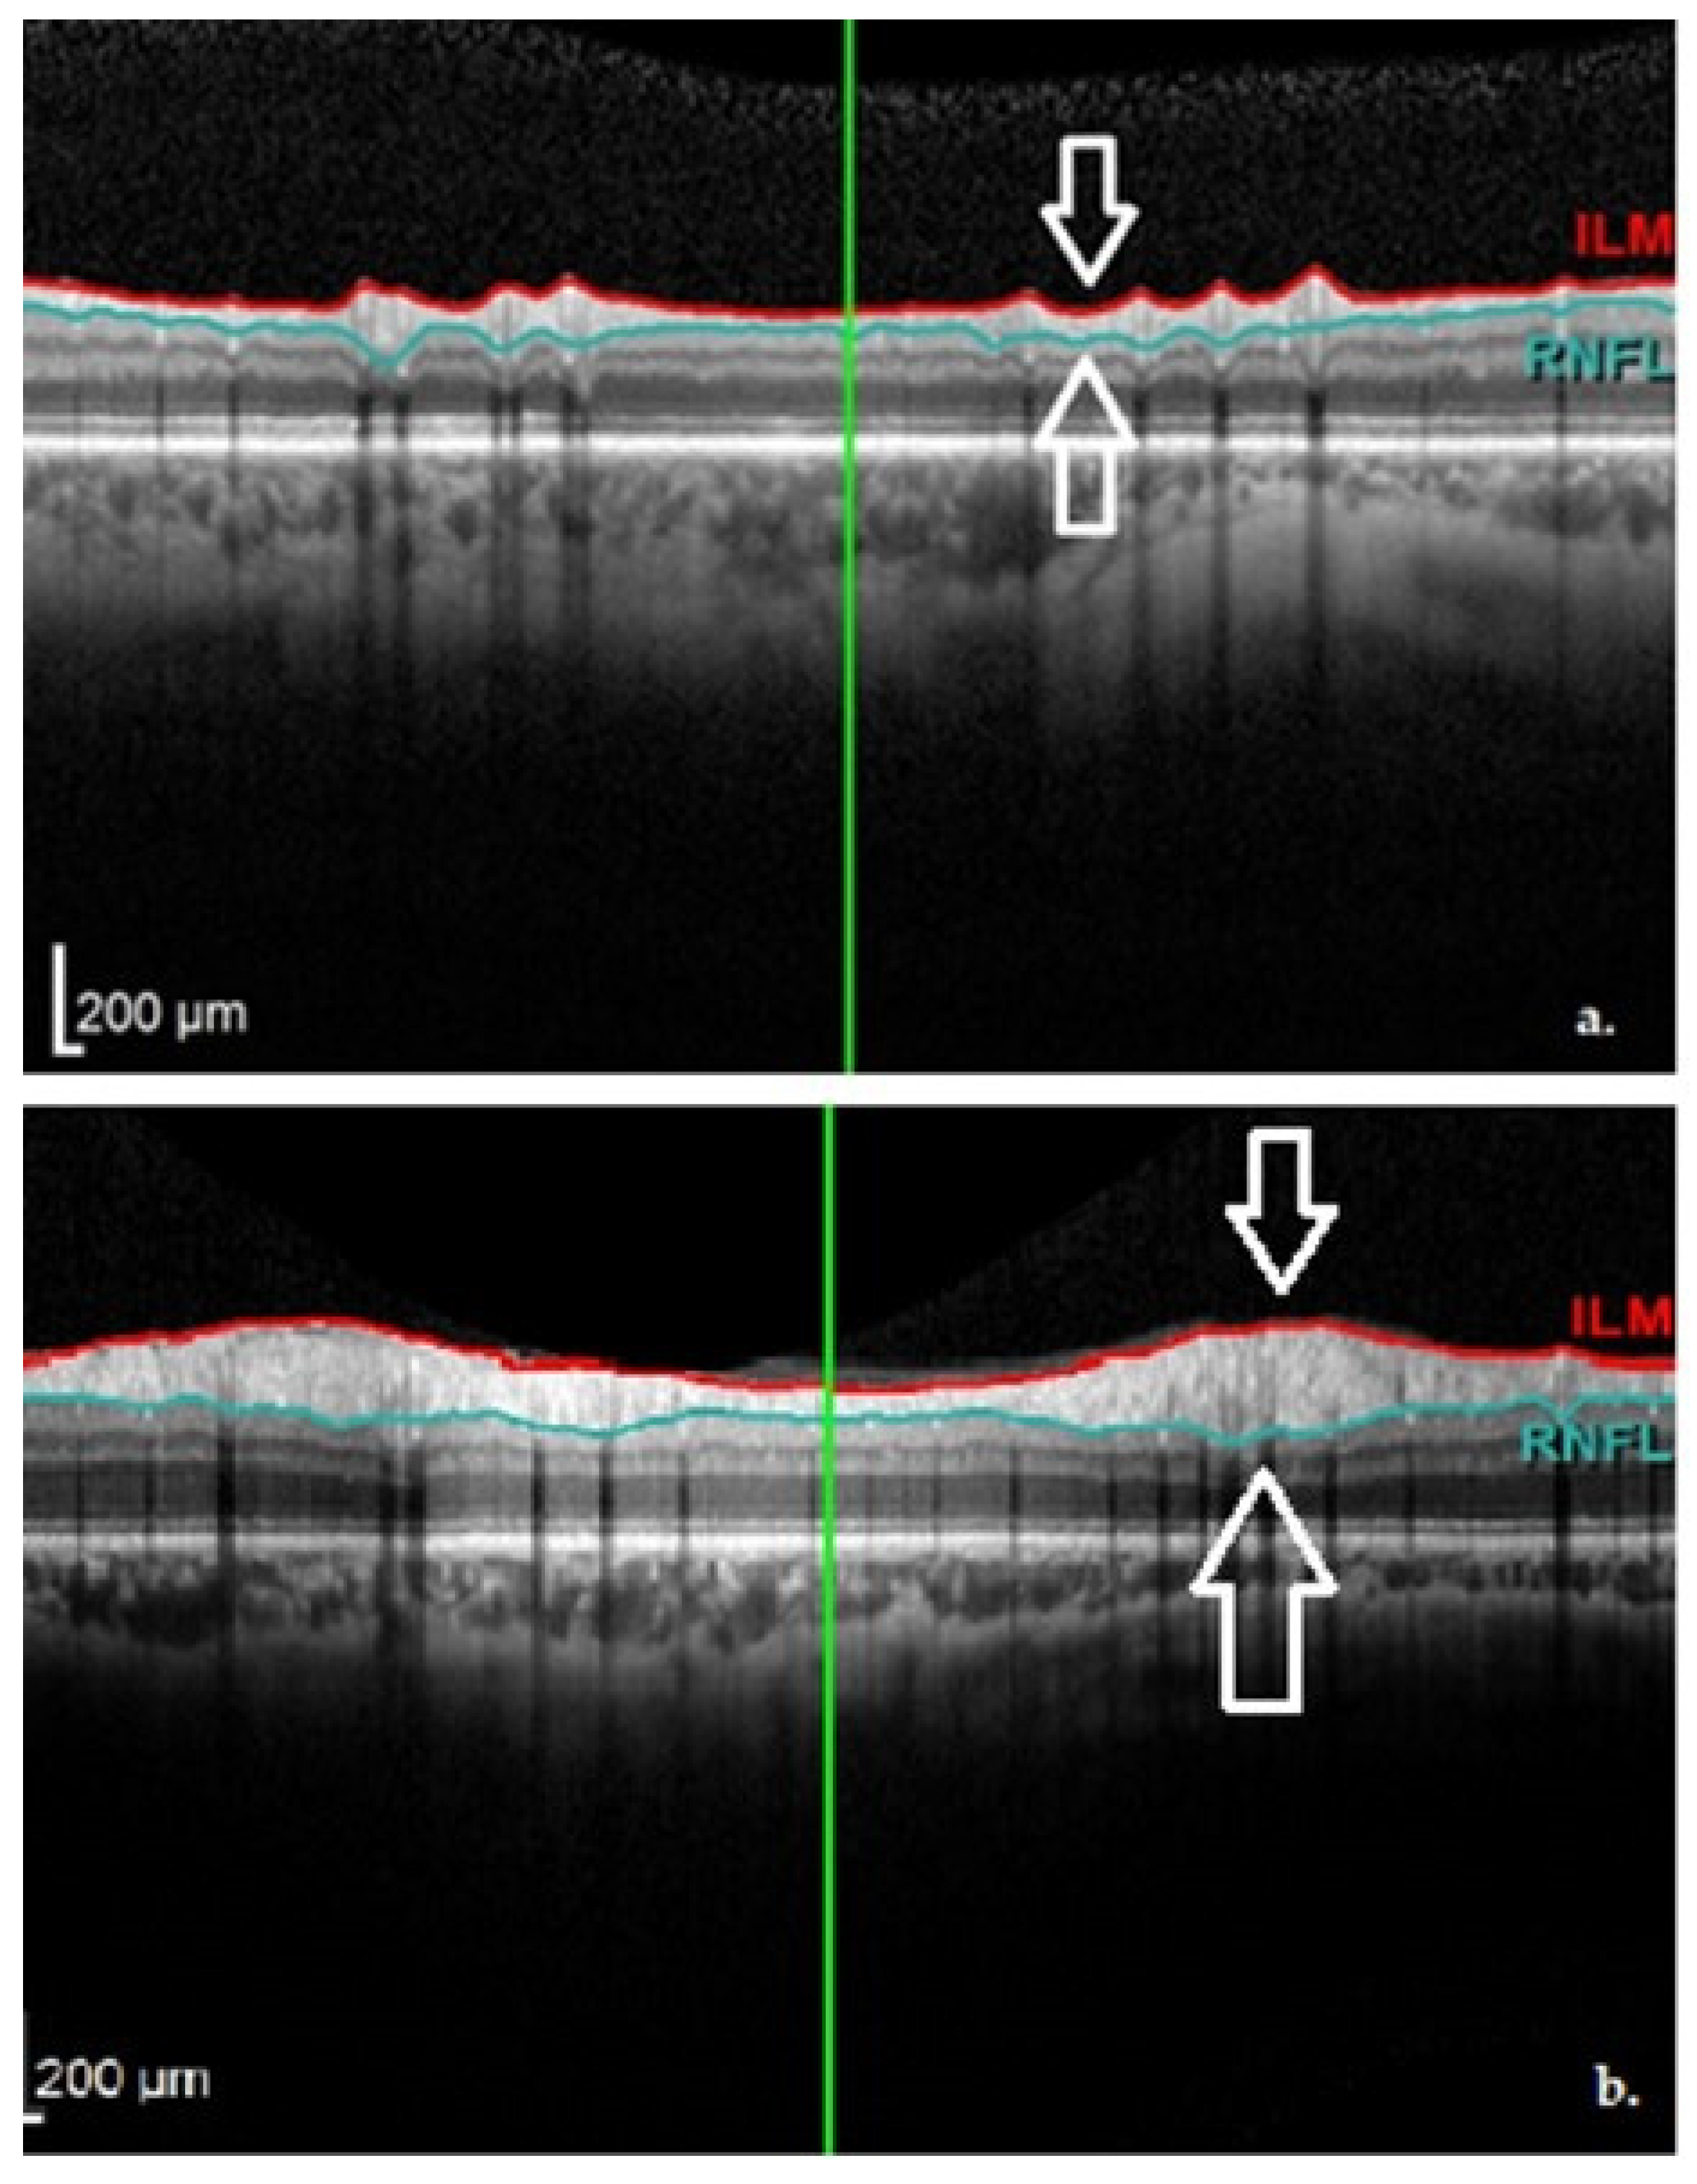

The main dopaminergic neurons in the retina are considered to be the amacrine and interplexiform cells. These neurons send axonal projections into the internal and external plexiform layers of the retina towards the horizontal cells. Thus, dopaminergic cell loss in the retina would generate a thinning of the inner retinal layers (see Figure 4), which could be detected by OCT [5,6,10,11,12].

Figure 4. (a) The Graphical Analysis of the cpRNFL values in a PD patient (note the black line); (b) The Graphical Aspect of the cpRNFL values in a normal subject (Images from our study). TMP—temporal; TS—superior-temporal; NS—nasal-superior; NAS—nasal; NI—inferior-nasal; TI—inferior-temporal.